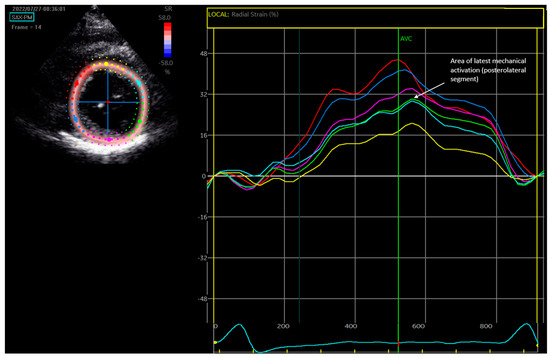

2.3. Speckle-Tracking Radial Strain Echocardiography

3.4. Comparing QLV and Radial Strain for Identification of the Area of Latest Activation

3.5. Comparing Sensed R-Wave Amplitude and Strain Amplitude Defined LV Scar